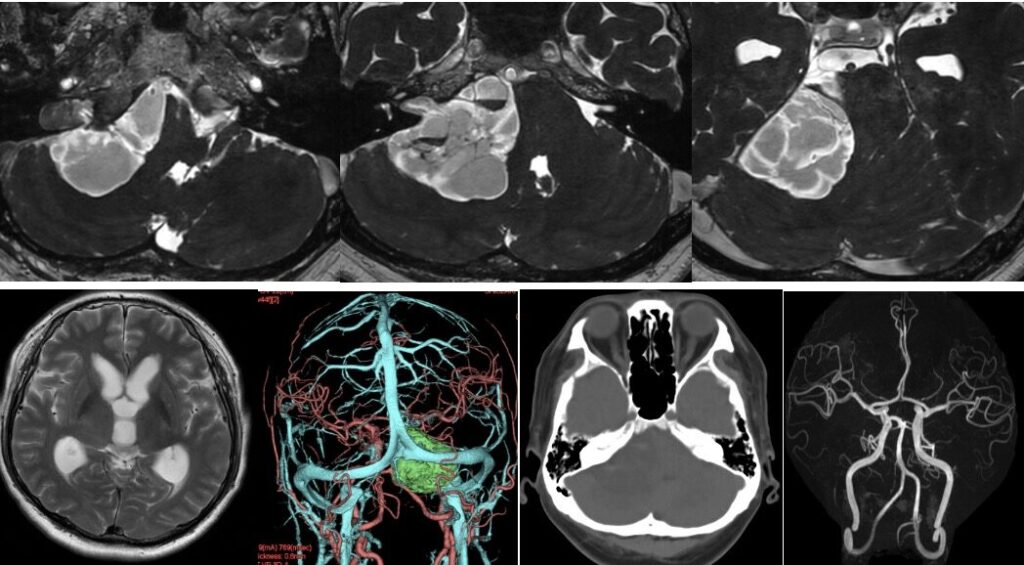

右顔面痺れ、聴力消失、ふらつき歩行障害が進行する50歳男性を、準緊急で手術しました。比較的出血の少ない腫瘍で15:30くらいには上がることができました。三叉神経はペラペラになっていたので周囲の腫瘍は残しました。顔面神経もペラペラでしたが珍しくcaudal typeで追跡が容易でした。内耳道内もきっちり取れました。手術後顔面麻痺、痺れとも大きな悪化なく腫瘍の大半は切除され会心の手術となりました。